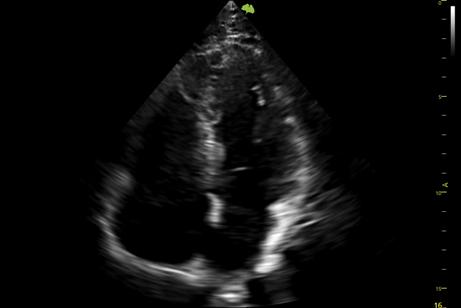

2. Công nghệ đầu dò XCen đơn tinh thể PureWave: Băng thông rộng hơn, Sóng tinh khiết, độ nhạy cao.

Vinno S100 còn được trang bị công nghệ đầu dò đơn tinh thể PureWave kết hợp XCen, mang lại băng thông rộng hơn, độ nhạy cao hơn và khả năng xuyên sâu tốt hơn. Nhờ đó, hình ảnh thu được không chỉ rõ nét mà còn chi tiết ở cả những vùng sâu trong cơ thể. Công nghệ Doppler màu tiên tiến cũng giúp đánh giá chính xác lưu lượng máu, hỗ trợ hiệu quả trong các trường hợp lâm sàng phức tạp.

Đầu dò PureWave Single Crystal & XCen cung cấp băng thông rộng hơn cho đầu dò tim đơn tinh thể S1-6PS (Option) nhằm: Cải thiện hiệu quả chuyển đổi, độ phân giải trục được cải thiện, độ nhạy được cải thiện giúp quan sát cấu trúc sâu hơn và hình ảnh rõ nét hơn.